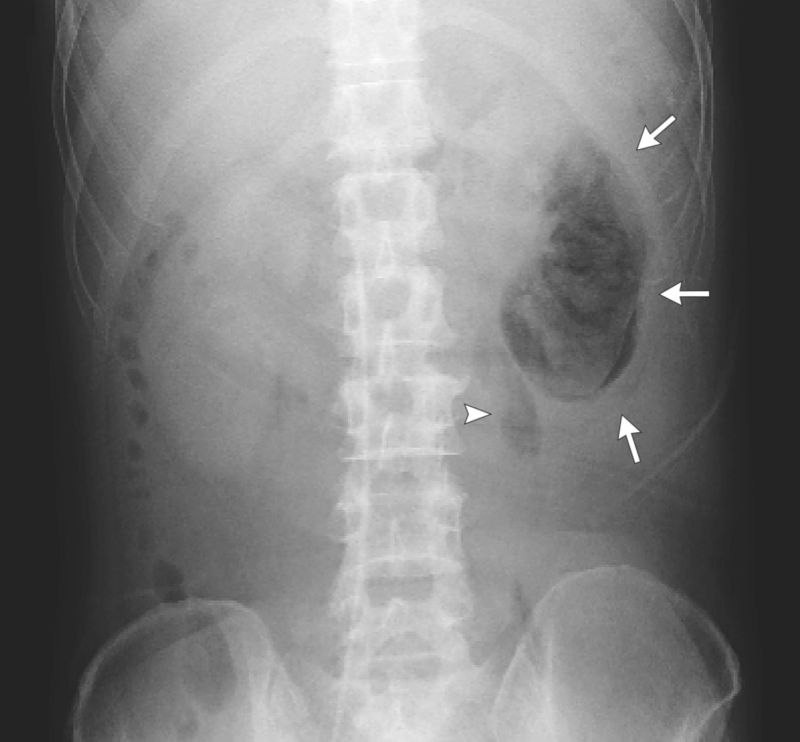

Patient with Diabetes and 2 Weeks of General Malaise and Fever Post category:Spot Diagnosis Post published:September 2, 2022 Share on Facebook Share on X (Twitter) Share on Pinterest Share on Email Share on Reddit Emphysematous Pyelonephritis on X-Ray and CT A 51-year-old male with diabetes presented with 2 weeks of general malaise and fever. What is the diagnosis? CLICK FOR FULL CASE AND ANSWER Share on Facebook Share on X (Twitter) Share on Pinterest Share on Email Share on Reddit Read more articles Previous PostPainless Periumbilical Masses in Patient with Type 2 Diabetes Mellitus Next PostPain and Swelling of the Left Thigh and Lower Leg You Might Also Like 26 Year Old Woman with Painless Nodular Skin Lesions October 12, 2021 Patient with Hypercalcemia and Suppressed Parathyroid Hormone Level October 4, 2021 Sharply Demarcated, Erythematous, Plaques Covered with Scales and Crust June 13, 2021